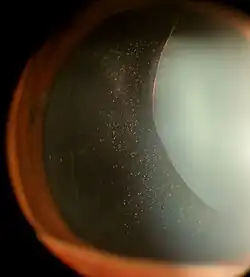

Ectopia lentis in a patient with Marfan syndrome. Zonular fibers are visible.